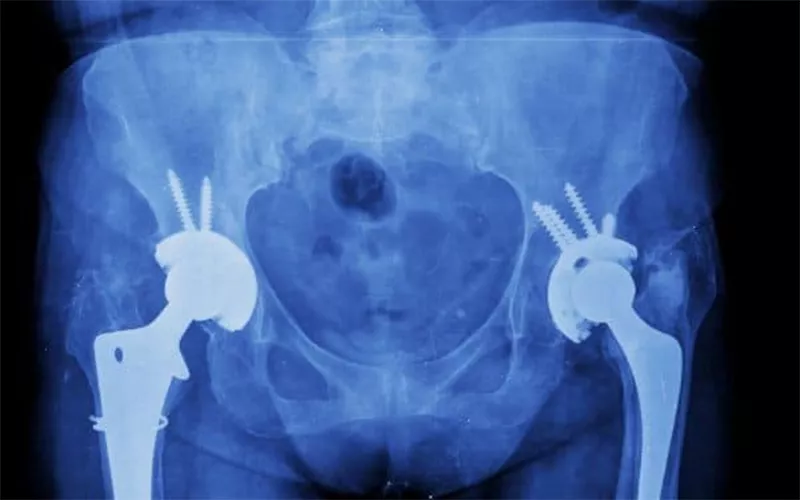

关节球头: 在骨科领域,氧化锆陶瓷的作用日益重要。氧化锆陶瓷可制成髋关节假体的关节球头,具有超低的磨损率和优异的生物相容性,能够提供超长的使用寿命和极低的过敏率。临床数据显示,氧化锆的十年保留率高达98%。

氧化锆关节球头

陶瓷假体: 在一些膝关节置换手术中,使用氧化锆陶瓷部件可以显著提高假体的耐磨性。其光滑的表面和稳定的化学性质可以减少磨损颗粒的产生,为您的关节置换手术提供更可靠的结果。